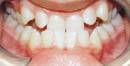

Hier können Sie einige Behandlungsergebnisse sehen

Mit dem Damon-System können wir Ihnen anbieten, was Sie wünschen - gerade und gesunde Zähne und ein wunderschönes Lachen auf schnellste und bequemste Art und Weise.

Diese zufriedenen Damon-Patienten erlebten alle eine gute Behandlungszeit - ohne das Ziehen von Zähnen, ohne einem Headgear oder rapid...

Tolle und schnelle Behandlungsergebnisse... |